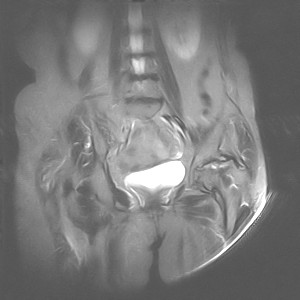

图像太差了 1、右侧臀肌旁脓肿? 建议增强 2、左侧股骨头坏死并半脱位

1、左侧股骨头坏死并髋关节半脱位;

2、右侧臀肌感染,(可能褥疮所致)